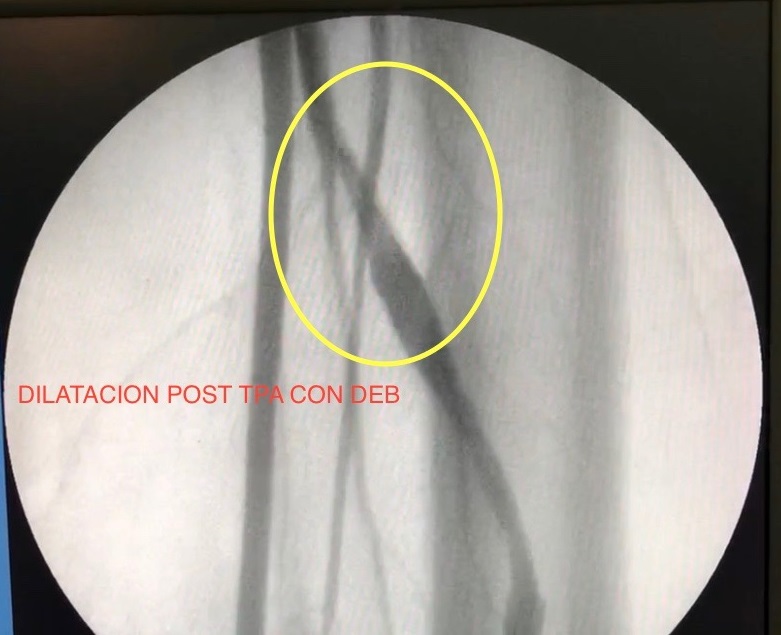

Se realizó una primera dilatación con balón simple de 5 x 60, durante 120 segundos continuos a 8 ATM. Control angiográfico: constató dilatación con pequeño flap de disección (Imagen 4). Se procedió a realizar angioplastía con balón con Paclitaxcel de 6 x 60 RANGER®, durante 180 segundos a 6 ATM, obteniendo resultado satisfactorio con buen flujo en el recorrido completo de todo el acceso sin necesidad de colocar stent.

Se obtuvo resultado satisfactorio con buen flujo en el recorrido completo de todo el acceso, mediante control angiográfico (Imagen 5 . 6).

Durante sus últimas valoraciones de funcionalidad destacó: FAV permeable, de adecuado desarrollo, accesible y de punción poco dificultosa; Kt/ve 1,86; presión prebomba -200 mmHg; presión venosa 200 mmHg; Qb nominal 400 ml/min; flujo efectivo (Qbef) 356 ml/min. Estos datos se mantuvieron constantes durante los últimos trece meses.